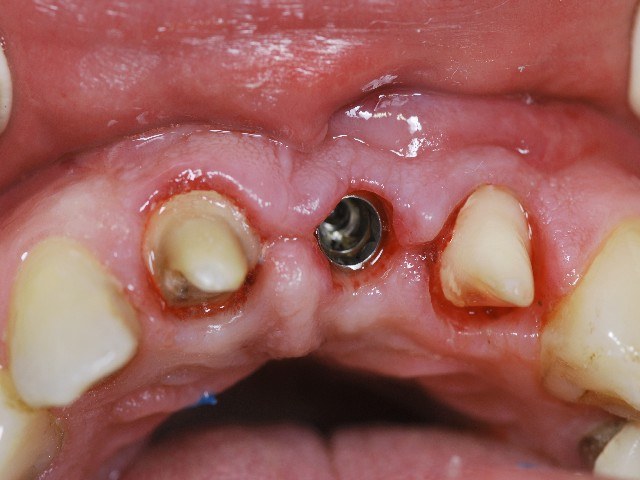

Bildserie : das Implantat nach dem Eröffnen könnte man mit einem Gewinde vergleichen

Auf das Abutment und die Nachbarzähne werden Zirkon Kronen gefertigt

Das Abutment wird mit dem Implantat verschraubt

Die metallfreien Kronen werden eingesetzt

Schon nach kurzer Zeit werden die Zirkonkronen durch Ihre Zahnfleischfreundlichkeit unsichtbar integriert statt einer Brücke wollen heute die meisten Menschen lieber ein Implantat das ist stabiler und langlebiger die Belastung wird gleichmäßig verteilt die Ästhetik ist viel besser.